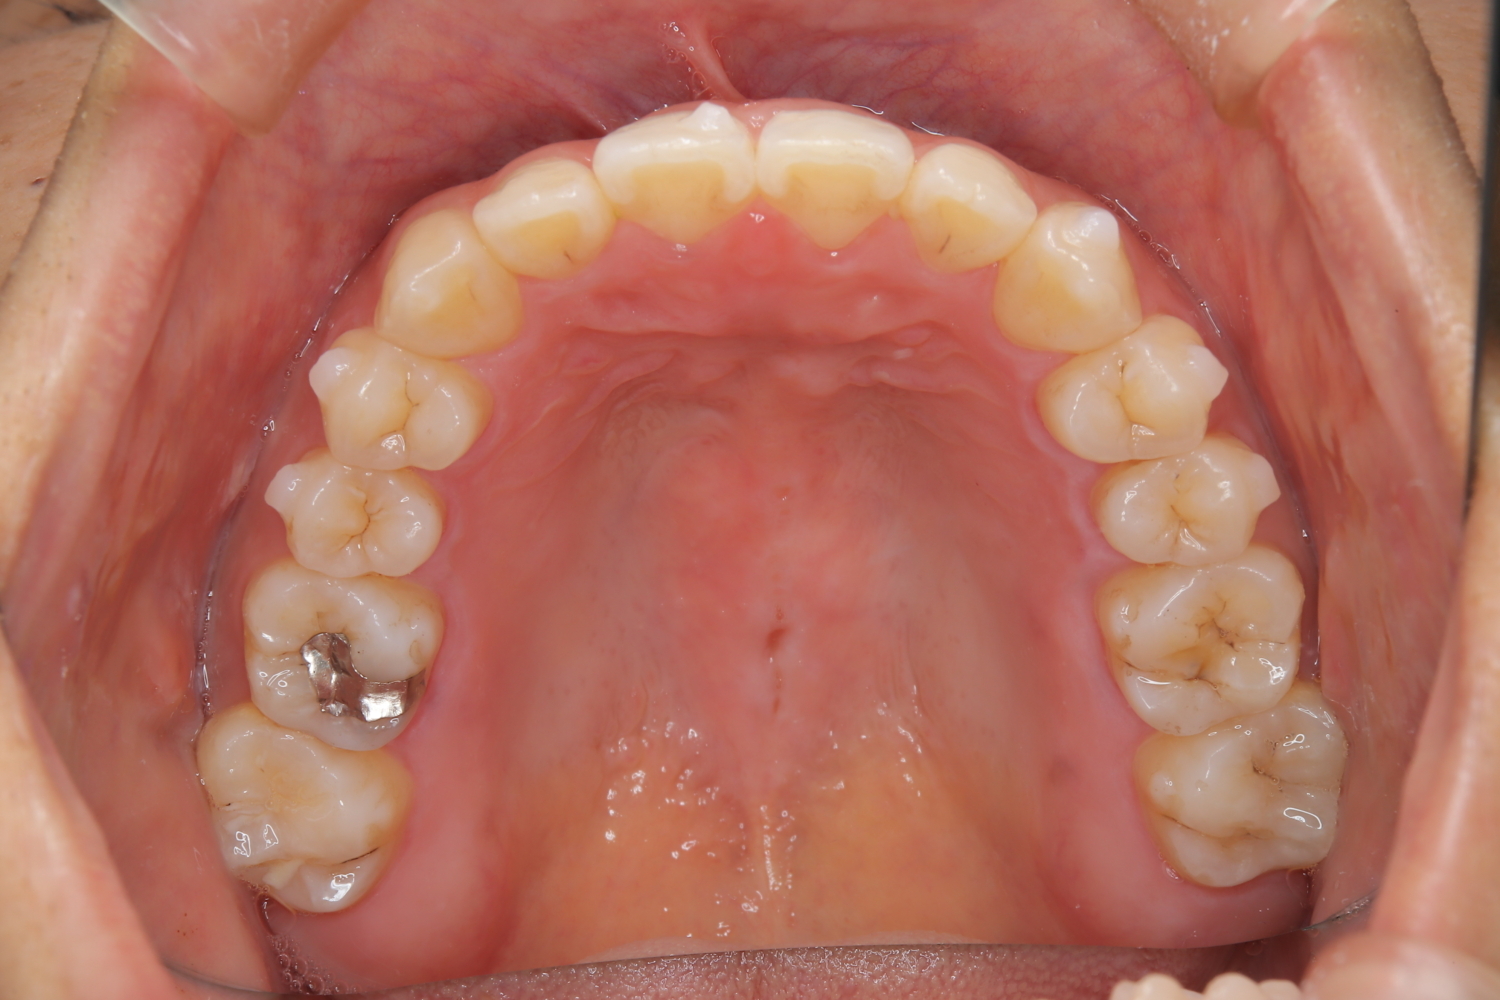

受け口の改善を主訴にご来院された患者様です。

軽度の下顎前突と診断し、マウスピース矯正装置(インビザライン)を用いて治療を行うこととしました。